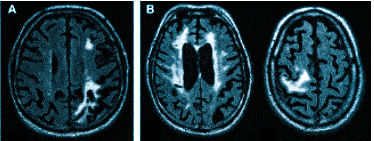

Множественные ишемические очаги при сосудистой деменции на МРТ: отсутствие памяти на недавние события и неадекватное поведение не являются признаками старости, своевременная диагностика деменции и патогенетическая терапия помогут замедлить прогрессирование болезни